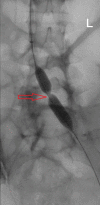

May-Thurner syndrome (MTS) is a rare clinical condition caused by extrinsic compression of the left common iliac vein by the right common iliac artery, leading to venous stasis and predisposing to thrombus formation. Here, we present the case of a 39-year-old female with no obviously known other risk factors predisposing to thrombosis who presented with severe left leg pain and swelling for a week. The international normalized ratio was elevated and the venous Doppler study showed extensive thrombosis extending from the left common iliac vein to the common femoral vein and the popliteal vein. She was diagnosed with MTS and treated with catheter-directed mechanical thrombolysis and thrombectomy, along with angioplasty of the left common iliac vein and external iliac vein, with near-complete resolution post-treatment. MTS should be suspected in patients who present with unilateral limb thrombosis regardless of the presence of predisposing factors. Timely management with endovascular procedures is necessary to help prevent other potential life-threatening complications.